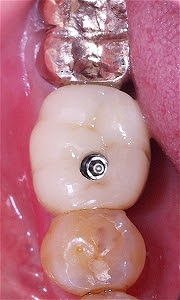

Pérdida de un diente único

La pérdida de un diente único es cuando un solo diente se ha caído o ha sido extraído, y se necesita un implante para reemplazarlo.

Los pacientes pueden notar un espacio donde solía estar el diente. Esta condición puede afectar la estética y la función masticatoria.

El tratamiento incluye la colocación de un implante dental para restaurar el diente perdido.